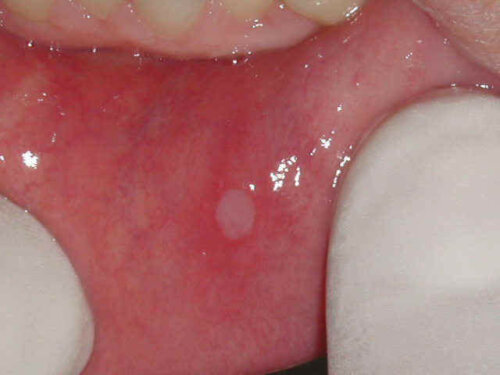

Disse læsioner består normalt af en enkelt rund, hvidlig læsion, der er omgivet af et betændt område. De er sjældent større end 8 mm.

Desuden kan der være mere end ét sår, og disse er normalt mindre end 3 mm. Der er også tilfælde, hvor disse læsioner er større, og helingen er mere kompliceret.